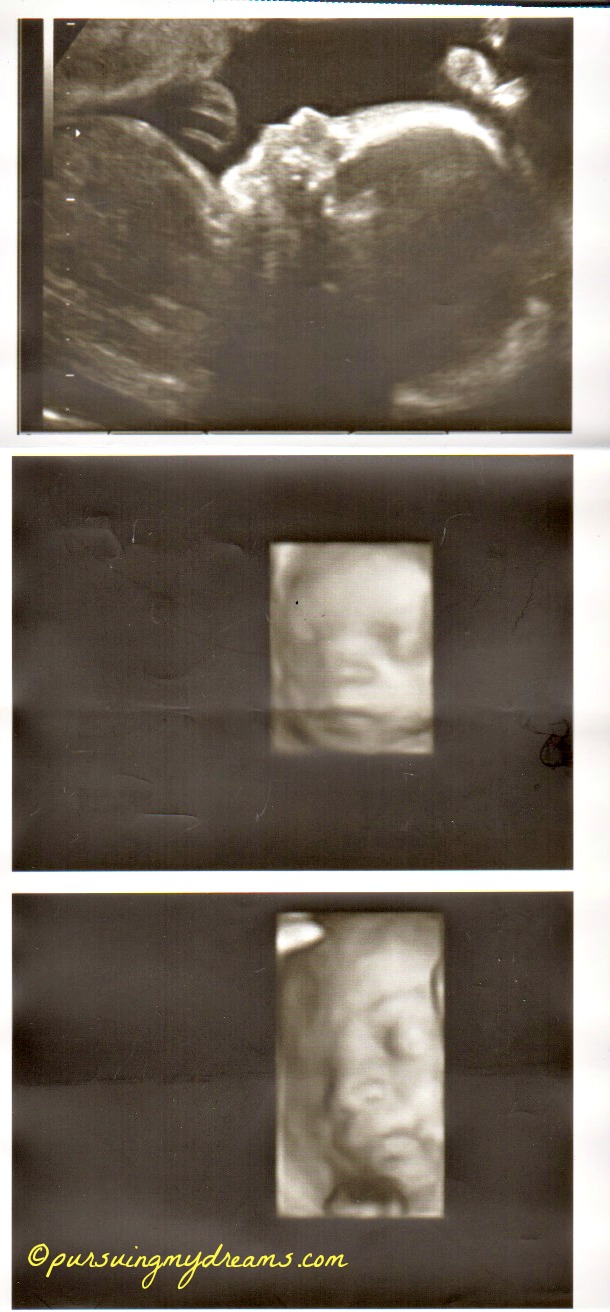

Sebagai penutup saya sertakan foto hasil usg anakku. Ini usg saat usia kehamilan 25 minggu. Dilakukan di kliknik Mannheim. Setelah itu sampai saat ini dokter tidak pernah melakukan pemeriksaan usg lagi karena semuanya baik-baik saja. Jadi hanya diperiksa posisi kandungan.

yang 2x karena aku ada pemeriksaan di klinik yg lebih besar Cha trus dikasih print out USG nya, klo di dokter biasa cuma 2x ga dikasih print out usgnya 😥 .

Mending mbak 3x disini kl hamilnya normal, mksdku gak melalui IVF kaya’nya cm 2x deh USG nya udh gt ya yang 2D itu doank, itu 4D kan mbak yah?? 36 mgg gak terasa ntar lagi bertiga deh kaliaaaan… Semoga sehat dan lancar ampe lairannya ntar ya mbak :*

Aku sdh 36 minggu nih. USG cuma 3 kali 🙁 pelit dokternya pdhl tiap kali ke dokter aku semangat pengen lihat si kecil kan.

Iya bang keliatan jelas, padahal itu masih 25 minggu. Ga tau saya usg apa namanya hehehe.

Hidung anakku ngikut aku Ndang alias pesek, dokternya bilang gitu 😆 .

wah… udah kelihatan jelas. itu pake uSG 3 dimensi yah? mirip sama buku ….. ah lupa judulnya… isinya seh kebanyakan foto perkembangan janin di setiap minggunya